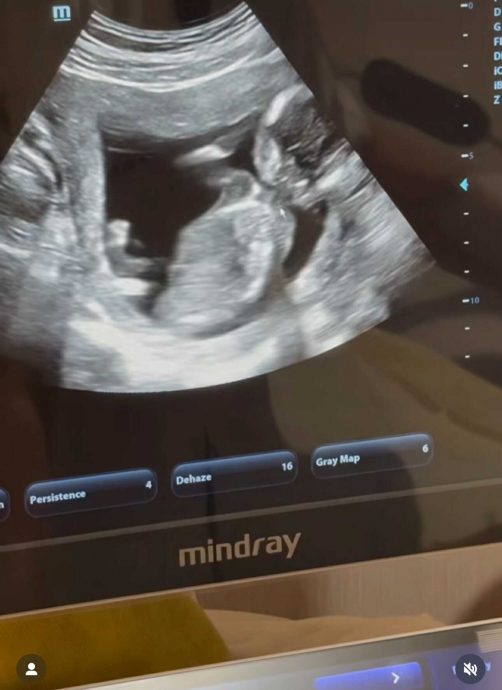

自曝预产期在年底

云镁鑫分享的视频中,可见阿哲给她送上一份生日礼物,里头竟然是超声波照片,并留言写道:“今年的‘生日礼物’已收到!但是。。要年底才能‘拆礼物’喔!”云镁鑫怀孕似乎没有要顾着身形,除了表示生日有双倍快乐,还开心喊:“我也可以吃双倍咯!”最后,不忘祝自己:“祝我生日快乐,祝我当妈快乐”,亦叮咛老公:“陈先生要努力赚奶粉钱喔!”